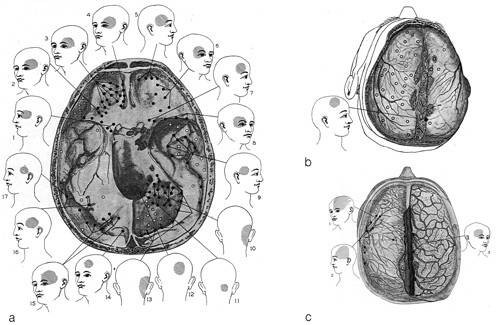

Konseptet om at hodepine kan skyldes irritasjon av meninger, er i alle fall 100 år gammelt (21), men kunnskapsgrunnlaget ble lagt av Ray & Wolff i 1940 (17). De gjorde flere hundre observasjoner på 30 pasienter under nevrokirurgisk behandling og registrerte i detalj hvor pasientene anga smerte ved ulike stimuli på ulike lokalisasjoner. Figur 2 viser den refererte smerten fra stimulering av dura mater på skallebasis (a), over konveksitetene (b) og langs større blodkar (c).